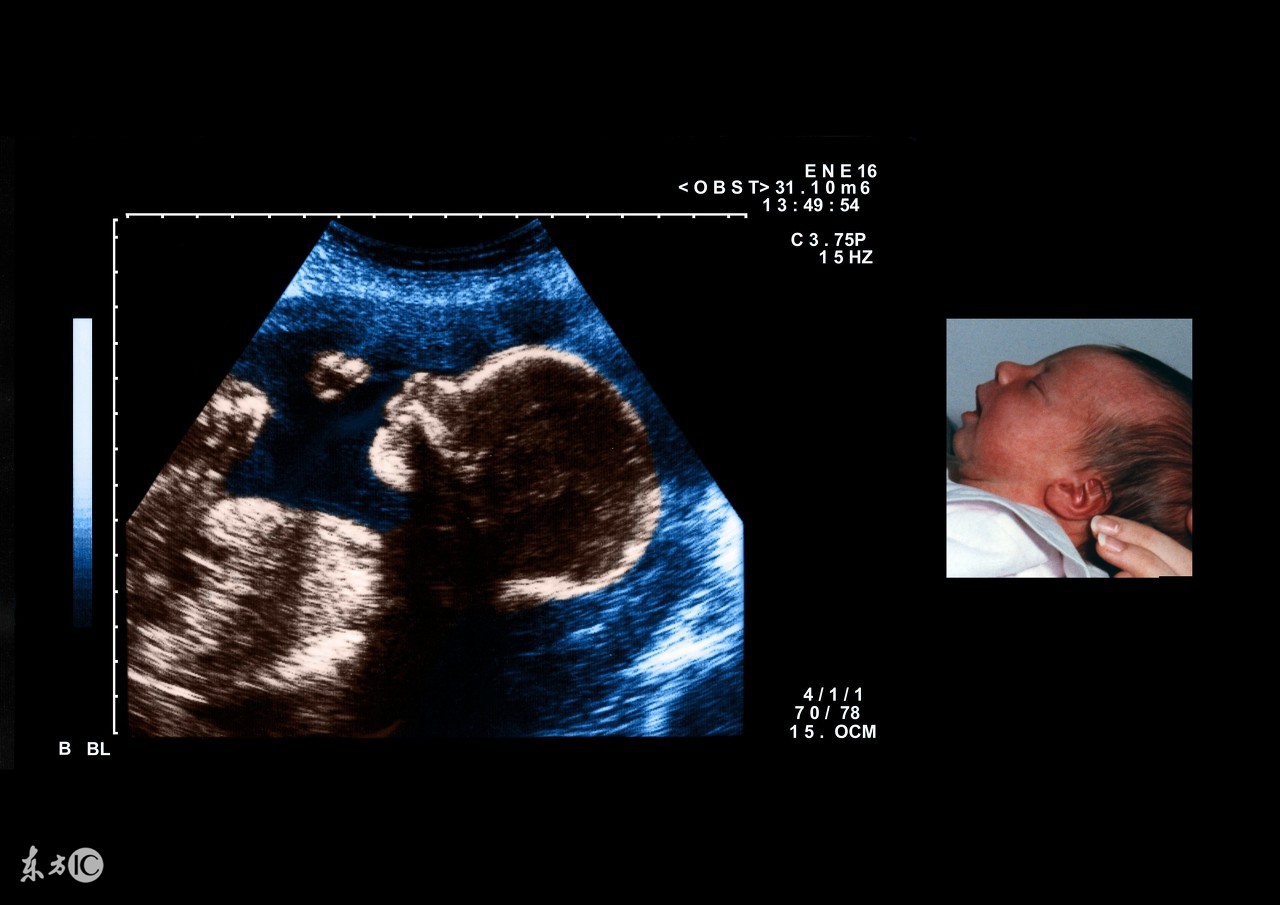

据统计,在自然流产中约有40%是由于胎儿染色体异常引起的。染色体异常的原因是多方面的,染色体异常与内分泌紊乱有关,特别是育龄较大的女性,很容易导致卵子染色体异常。除此之外,滥用药物、大气污染、饮食污染、电磁波污染、放射线污染等,也是导致染色体异常的常见因素。